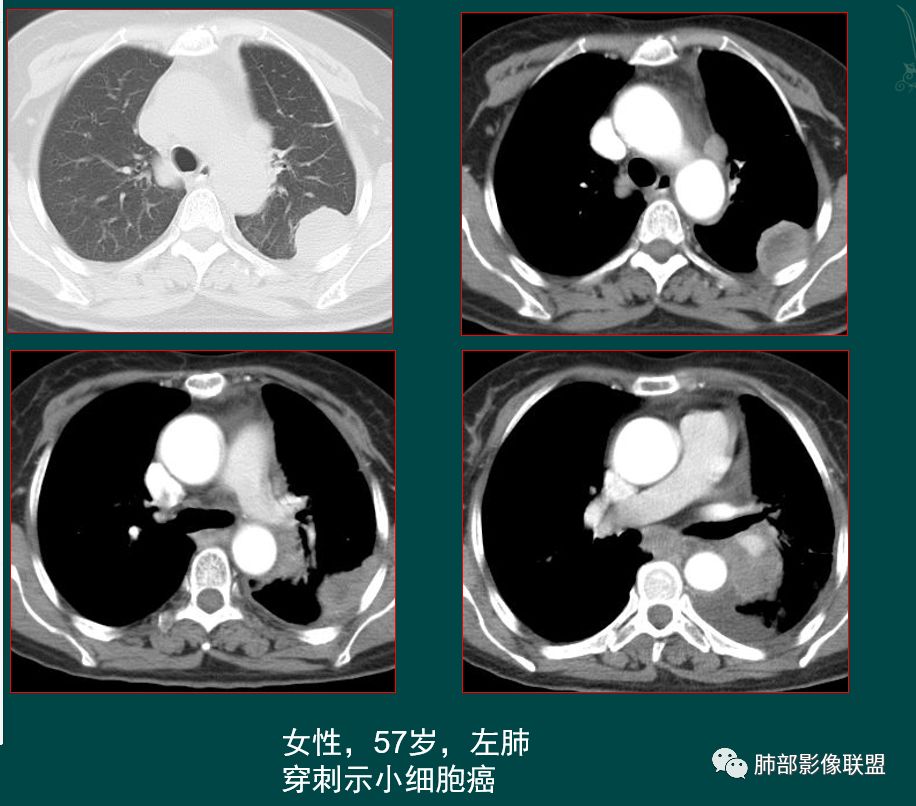

小细胞肺癌SCLC起源于支气管粘膜下,沿支气管粘膜下及周围血管生长,病理上SCLC细胞较小,胞质很少,粘附力差,肿瘤质软,细胞密集,增值快,侵袭生长,坏死小,常不彻底,破坏力弱。

有人认为SCLC以周围型多见,部分周围型SCLC因借肺门显著增大的淋巴结而摇身一变,以“中央型”的姿态出现在我们的视野中。

1鸭蹼状突起、腊肠样尾巴、指状突起、蠕虫、分支及条状

因为病灶沿支气管粘膜下及周围血管生长,走形方向与支气管一致,所以支气管血管周围生长也是SCLC的典型征象;

2娘小崽大、淋巴及血行转移早、冰冻纵隔及肺门血管脂肪间隙消失

因为病灶侵袭力强,病灶易沿淋巴道、间质及心血管间隙等结构侵犯并密切挤压上述结构,常常能够观察到脂肪间隙消失。易于出现冰冻纵隔。原发灶与肺门转移灶可形成哑铃状外观,甚至转移灶体积大于周围原发灶,有人称之为“娘小崽大”。早期病灶有时很小甚或隐匿,仅能看到转移灶,或转移淋巴结与原发灶融合分界不清。病变向肺门延续的串珠样淋巴结转移也是SCLC的典型特点。

病灶侵袭力强大,早期沿粘膜下疏松结缔组织及血管旁间隙扩散,包绕血管,间隙消失,血管会受压变形,因为小细胞癌破坏力弱,血管没有被破坏,所以仅仅表现为包埋浸润,但血流面光滑。

乏血供,沼泽样坏死

、罕见空洞

病灶肿瘤密集而供血血管相对不多,密度较均匀,轻度强化,呈乏血供,有时候可以坏死,坏死不彻底,坏死区分散而较小,呈沼泽样坏死。很难造成较大范围引流支气管的破坏,所以空洞罕见。

发生于肺边缘的小细胞癌有时会呈半圆形或圆冠状贴服于胸壁下,有老师称之为“山丘征”。经治疗后复查持续存在或增大的山丘影应当想到小细胞肺癌的可能性,尤其是在肺门纵膈淋巴结增大时。